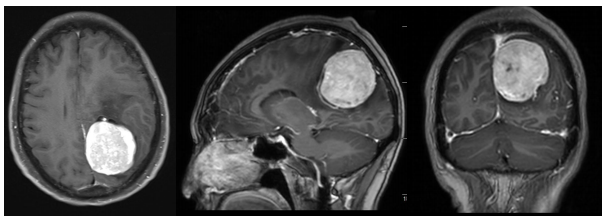

【948交通广播】眼红背后藏致命危机,“较真医生”这一举动救了17岁少年

17岁少年小林因眼白突发一片鲜红就医。本以为只是普通结膜下出血。却意外被医生揪出致命隐患——严重肾衰竭。发现小林除右眼出血外。结果在未出血的左眼眼底发现特征性Roth斑(中心白点、周围出血)及火焰状出血点。同时观察到...